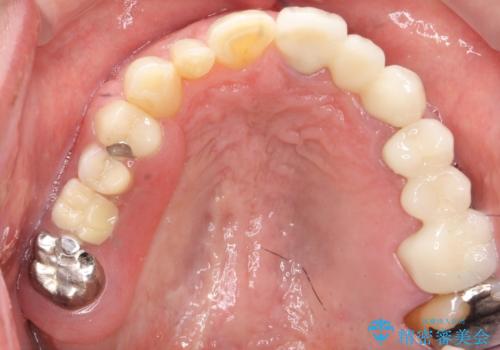

歯の牽引後、ブリッジの仮歯で保定しながら歯肉・骨の治癒を待ったのち、ブリッジによる補綴を行いました。

ご希望により最終補綴前にホームホワイトニングを行っております。

最終補綴前に右上321の結合組織移植術(CTG)を希望されたため、大元院長に行って頂きました。

牽引により歯の保存が可能となり、ブリッジによる補綴を行うことができました。

健全歯質を歯肉縁上に出すためにしっかり挺出させたことで歯根長が短くなりましたが、仮歯で十分に保定した結果動揺度Ⅰ程度となり、ブリッジの支台歯にすることが可能と判断しました。